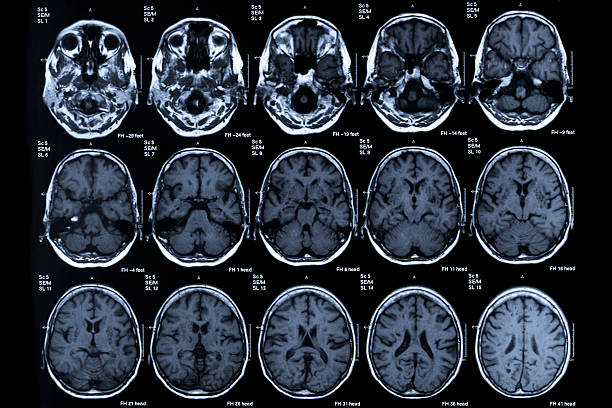

뇌 일부분에 혈액이 제대로 공급되지 않으면 혈관이 막히거나 터지기 때문에 뇌가 손상되며 여러 이상이 발생할 수 있는데 이러한 증상을 일컬어 뇌졸중이라고 합니다. 뇌졸중을 유발하는 원인에는 비만, 불규칙한 생활습관, 고혈압, 흡연 등으로 유발될 수 있으며 나타나는 전조증상들이 어쩌면 가볍게 넘길 수 있는 증상들이 많다보니 단순히 노화로 인한 증상으로 가볍게 여기는 경우도 있기 때문에 초기 대응이 어렵습니다. 따라서 이번 시간을 통하여 뇌졸중 전조증상에 대해 자세히 알아보고 초기 대응력을 높이시기 바랍니다.